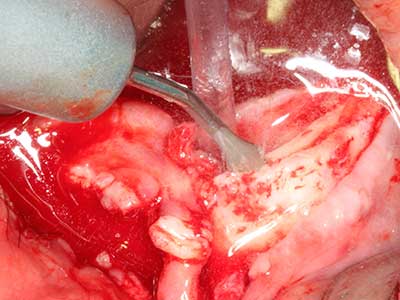

Piezo surgery has additional advantages when harvesting bone blocks. In addition to the high precision with osteotomy described above, the use of the thin saw tips specifically minimizes loss of material. Greater loss of material during harvesting can be expected with the thicker instrument tips, particularly when using Lindemann drills (Lakshmiganthan, Gokulanathan et al. 2012). The basal separation, which is necessary particularly for retromolar block transplants, is simplified by specially designed rectangular saws, with the result that piezo surgery is viewed as a precise, simple and safe procedure for harvesting retromolar bone blocks (Happe 2007) (Fig. 1-12).